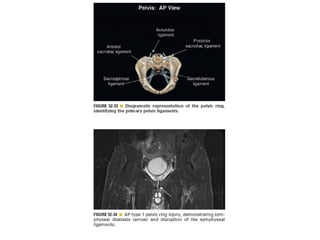

Skeletal trauma was presented by Dr Laith Fadhel with reference to Grainger's Diagnostic Radiology textbook. The presentation covered skeletal trauma as assessed through diagnostic radiology techniques. Key findings and treatments for skeletal injuries were likely discussed.